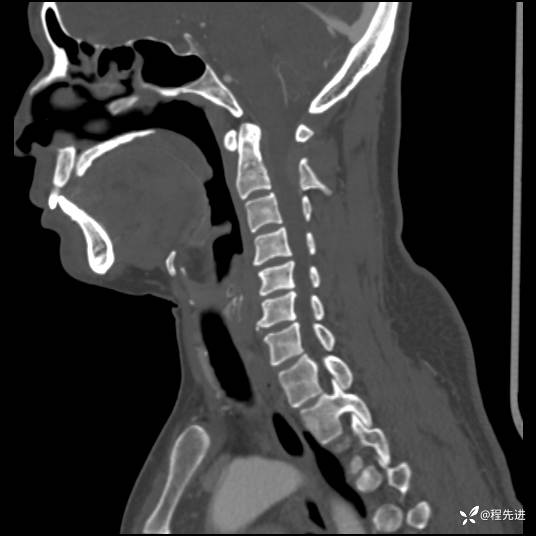

CT平扫+增强: